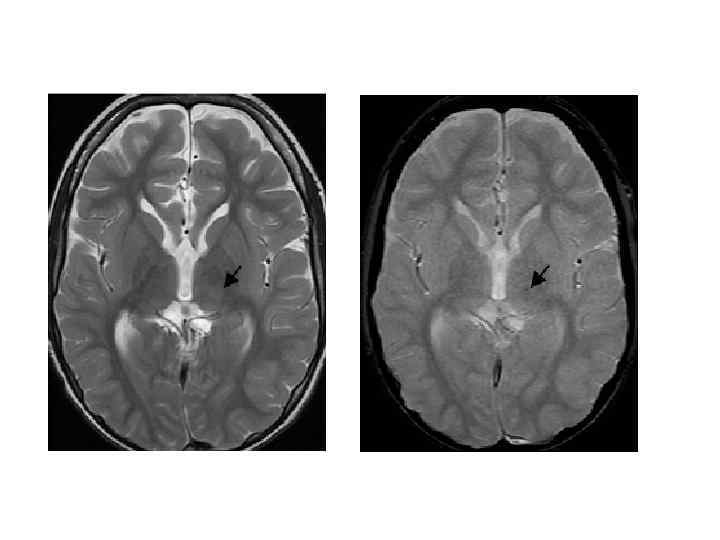

Церебральная кавернозная венозная мальформация (кавернозная гемангиома) • • 48 – 86% - в полушариях 5 – 13% сосудистых мальформаций ЦНС Манифестирует в 40 -60 лет Клиническая картина: обмороки (60%), неврологический дефицит (50%), кровоизлияния (20%), гидроцефалия (50%)